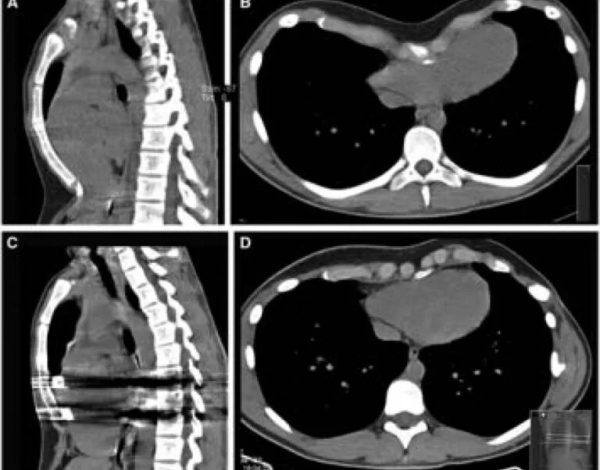

Arritmias ventriculares resueltas por corrección de pectus excavatum

Joven basketbolista en una ciudad de Portugal, es sometido a cirugía de corrección de pectus excavatum, como medida terapéutica de las arritmias ventriculares que padecía.